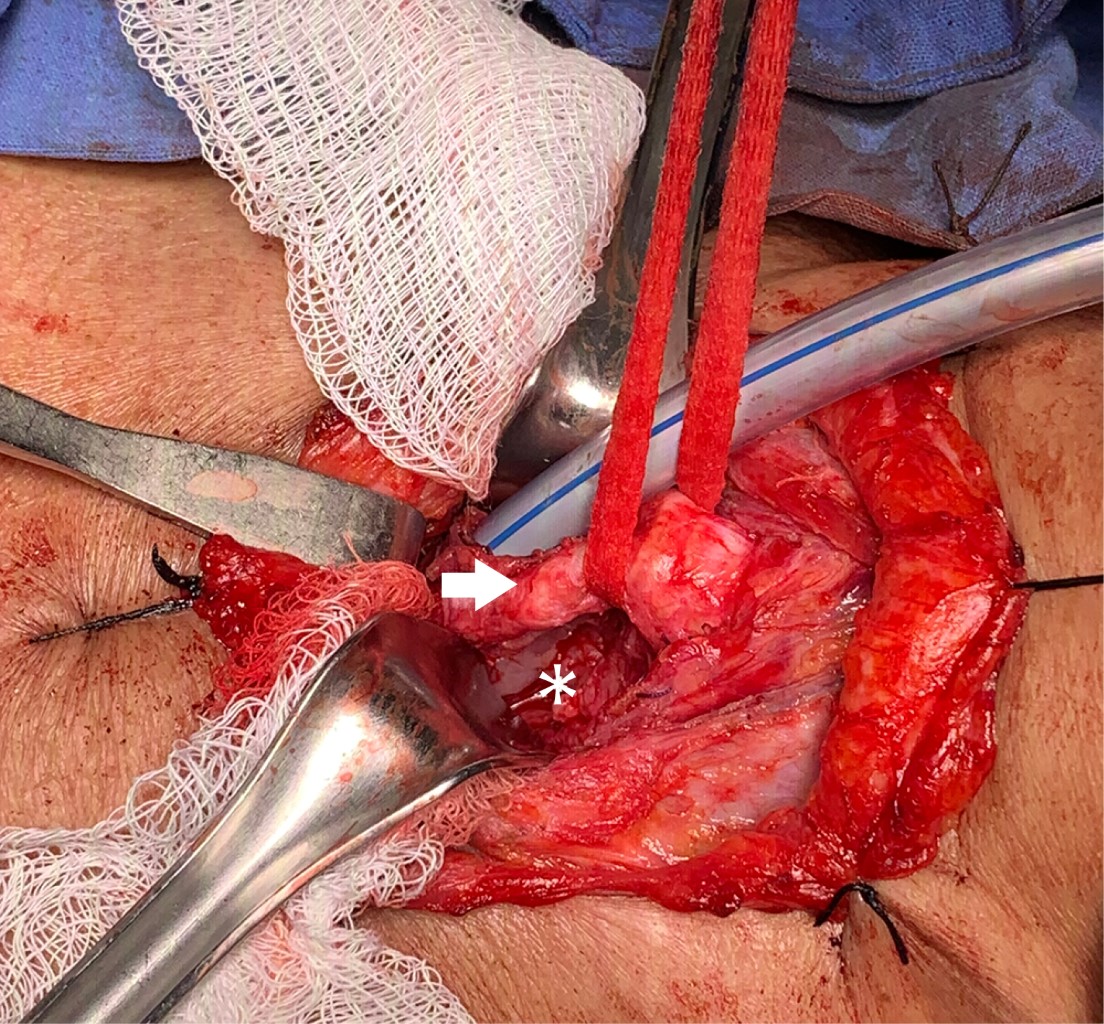

Femenino de 62 años con antecedente de diabetes mellitus e hipotiroidismo. Inició con síntomas sugestivos de COVID-19 el 21 de octubre de 2020, acudió a hospital general ocho días después con datos de insuficiencia respiratoria, se realizó tomografía computarizada y prueba de hisopado PCR para SARS-CoV-2 con resultado positivo; se decidió intubación orotraqueal. Adecuada evolución y extubación a los 10 días con mal manejo de secreciones y estridor laríngeo, con necesidad de reintubación 24 horas posteriores. Segunda extubación por mejoría clínica a los cuatro días; sin embargo, se agregó disfagia, por lo que se realizó esofagograma con evidencia de fístula traqueoesofágica. Se colocó endoprótesis esofágica y sonda de gastrostomía por el servicio de endoscopia. Presentó evolución tórpida y un mes después desarrolló deterioro neurológico y desaturación requiriendo nueva intubación orotraqueal. Se programó fibrobroncoscopia de revisión por Servicio de Cirugía de Tórax del INER una semana después por sospecha de estenosis traqueal, observando secreciones espesas y prótesis esofágica migrada en porción proximal de tráquea (Figura 1). Se identificó fístula traqueoesofágica (Figura 2) en pared membranosa de la tráquea de 4 cm, se realizó traqueostomía percutánea a nivel del cuarto anillo traqueal dejando rama distal de la cánula a 1 cm de carina principal. Al cabo de 10 días se retiró apoyo con ventilación mecánica. Se egresó a domicilio el 25 de enero de 2021 con nutrición enteral.

Se realizó nueva fibrobroncoscopia el 26 de abril de 2021 con hallazgo de fístula traqueoesofágica a 4 cm de cuerdas vocales de 4 cm de longitud, tráquea con 10 anillos traqueales libres a carina principal, por lo que se decidió ingresar a la paciente a nuestro instituto para manejo quirúrgico realizando cierre de fístula traqueoesofágica más cierre de estoma traqueal y colocación de traqueostomía en segundo anillo traqueal; se dejó cánula Portex 7 fenestrada sin globo. Se realizó un abordaje por cervicotomía transversal con hallazgos transoperatorios de abundantes adherencias paratraqueales y paraesofágicas, fístula traqueoesofágica de 3 cm de longitud (Figura 3). Cierre de esófago con sutura PDS 3-0 y cierre de pared posterior de tráquea con misma sutura con interposición de colgajo de músculo esternotiroideo entre ambos (Figura 4), estoma traqueal previo a nivel del cuarto anillo traqueal, el cual se recolocó a nivel de segundo anillo traqueal (Figura 5) y sangrado transoperatorio mínimo. Evolución posquirúrgica adecuada. Se realizó esofagograma de control a los siete días sin evidencia de fuga y con adecuado pase del medio de contraste (Figura 6). Se inició dieta con adecuada tolerancia y se egresó al día ocho posoperatorio sin complicaciones.